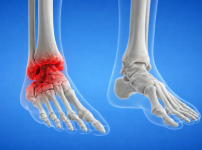

발목 관절염(Ankle arthritis) | 서울건우 | 의학정보

정의발목 관절염은 발목 관절을 보호하고 있는 연골이 마모되면서 뼈와 뼈가 직접 맞닿아 염증, 부종, 통증을 유발하는 질환입니다. 무릎 관절염에 비해 발생 빈도는 낮은 편…